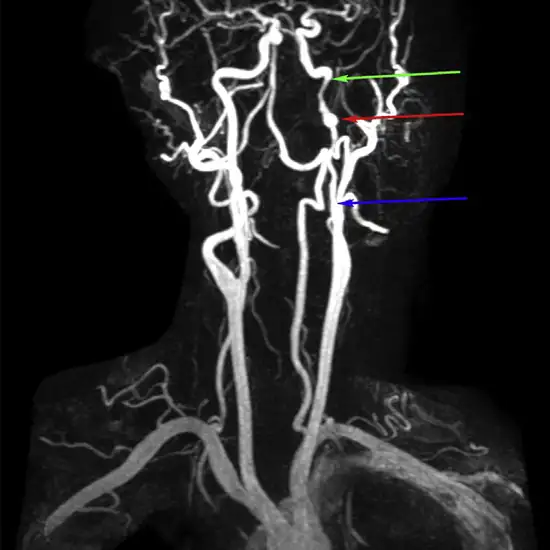

Carotid MR Angiography (MRA) is a non-invasive diagnostic imaging procedure that uses a combination of magnetic fields, radio waves, and contrast dye to visualize the carotid arteries. This procedure is used for analyzing the carotid arteries for blockage and narrowing. It helps in detecting the problems in carotid arteries which are the primary vessels that supply blood to the brain.

MRA (Magnetic Resonance Angiography) screening of the Carotid arteries is a non-invasive radiology test used to evaluate the condition of the Carotid arteries and surrounding tissue. Carotid MR Angiography is done to look for Carotid artery conditions and the surrounding area.